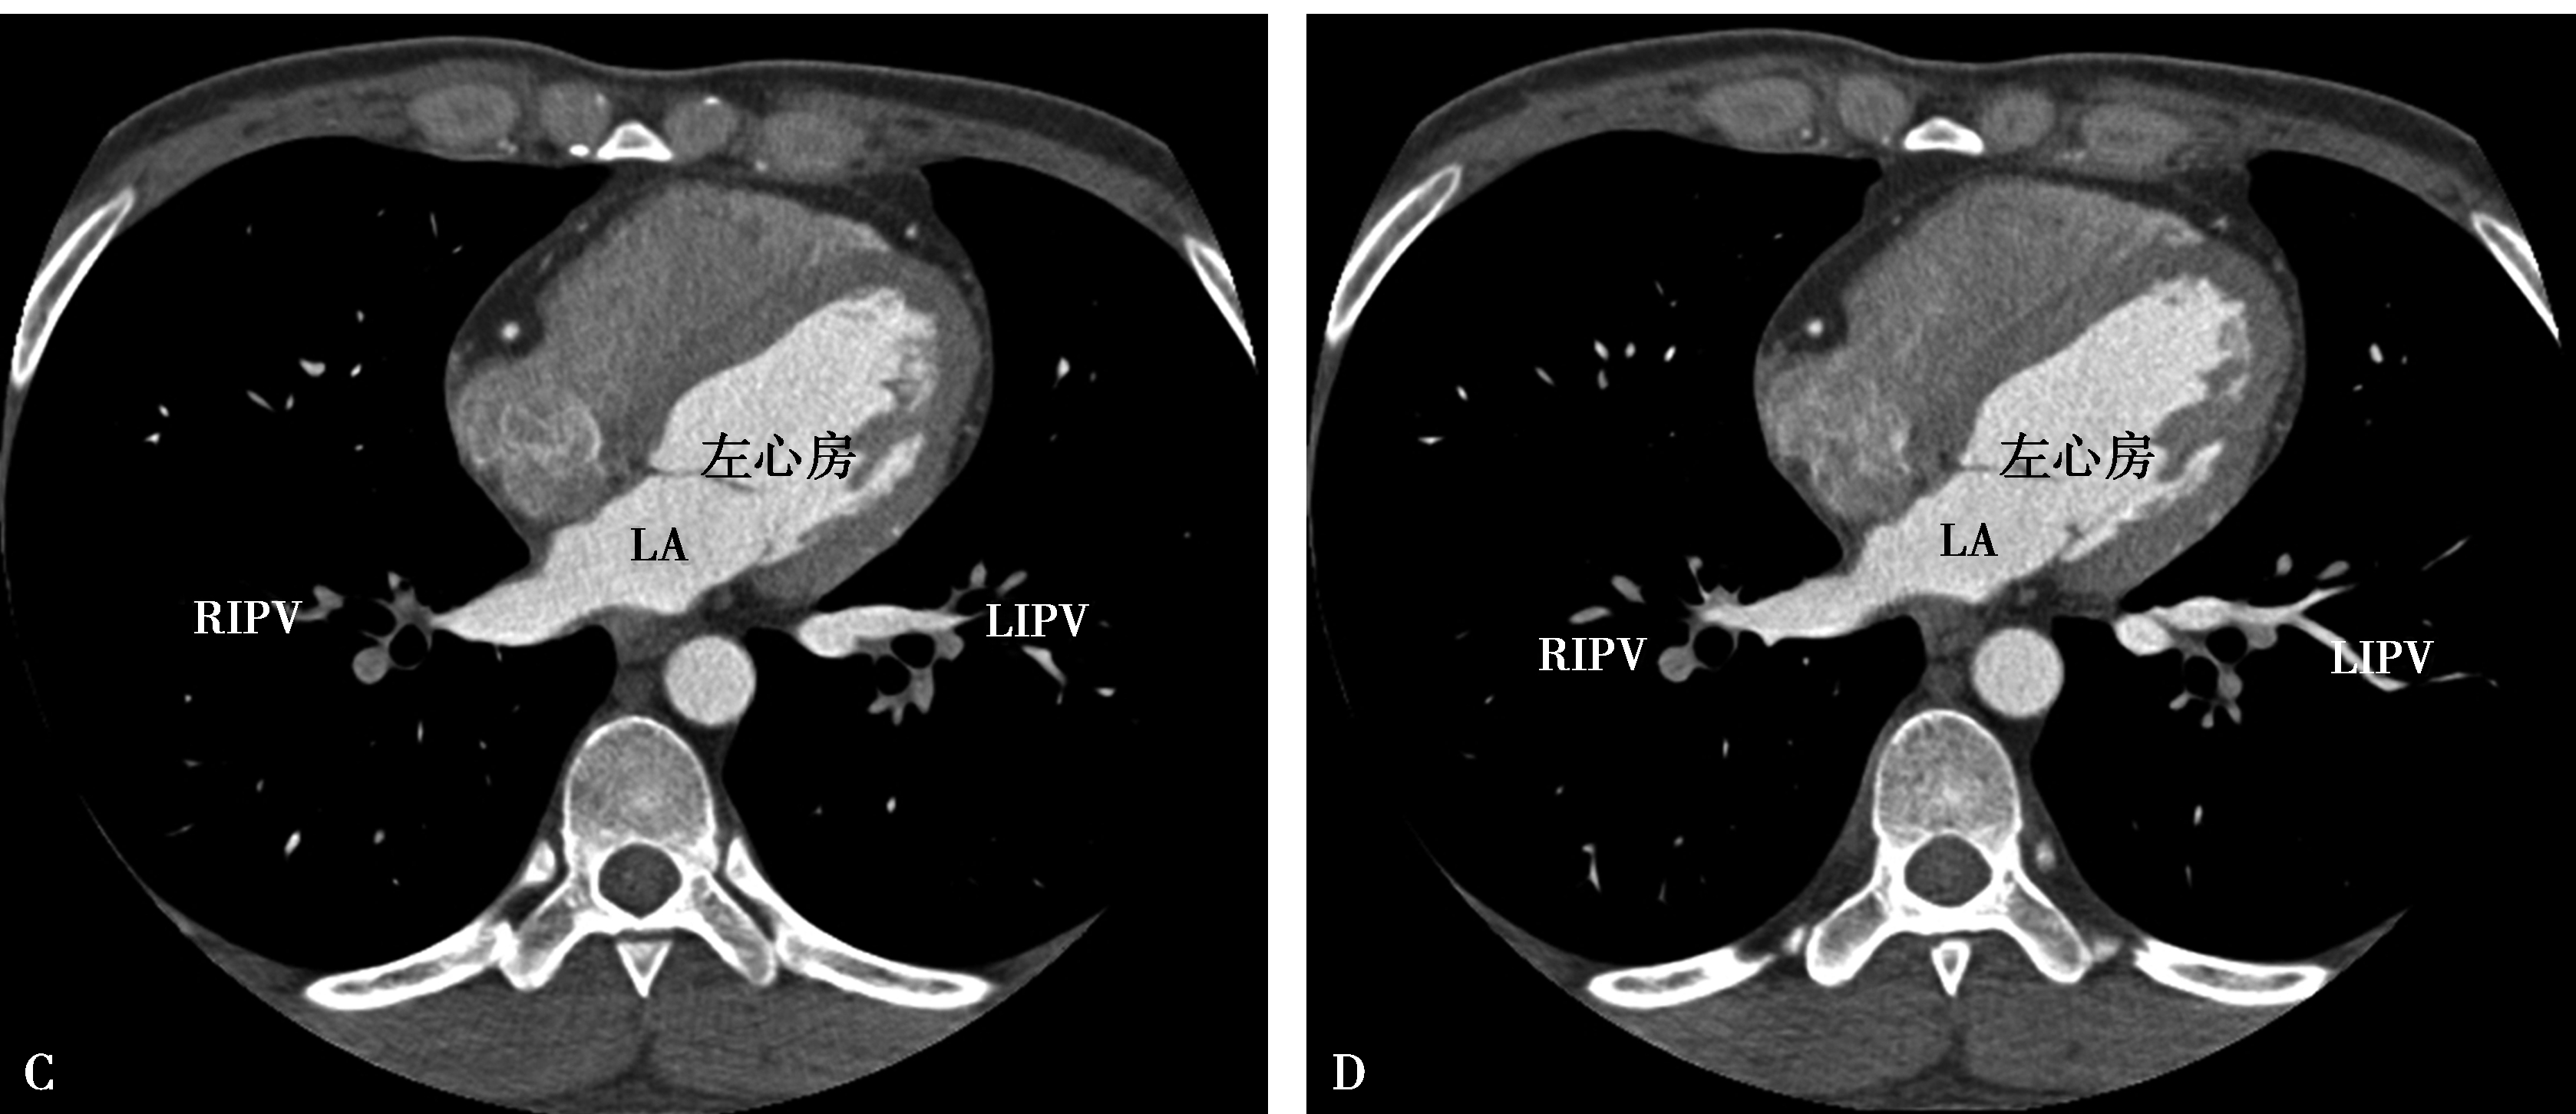

图8-1-11 肺静脉CTA检查

A.上肺静脉(↑);B.下肺静脉(↑);C.肺静脉最大密度投影。LSPV:左上肺静脉;LIPV:左下肺静脉;RSPV:右上肺静脉;RIPV:右下肺静脉